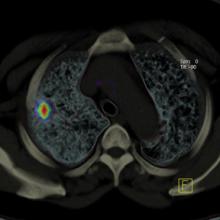

June 11, 2009 – PETNET Solutions, a subsidiary of Siemens Medical Solutions USA Inc. that manufactures and distributes radiopharmaceuticals, has signed a supply agreement with Lantheus Medical Imaging Inc. to provide BMS747158 for PET imaging of cardiac perfusion as part of the phase II and phase III trials.

The aim of every radiation oncologist when treating a patient is to deliver radiation dose as accurately as possible. To better hit their mark, clinicians are relying increasingly on imaging to guide them to the target, which in the case of prostate cancer is often a moving target. Accordingly, the role of imaging in this year’s NCCN Prostate Cancer Guidelines was a critical component.